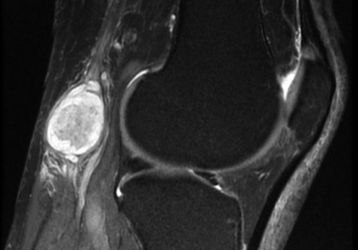

Киста в коленном суставе: лечение, симптомы, диагностика, виды кисты

Что такое киста коленного сустава, какие виды кисты существуют, характерные симптомы заболеваний. Диагностика и методы лечения кисты коленных суставов.